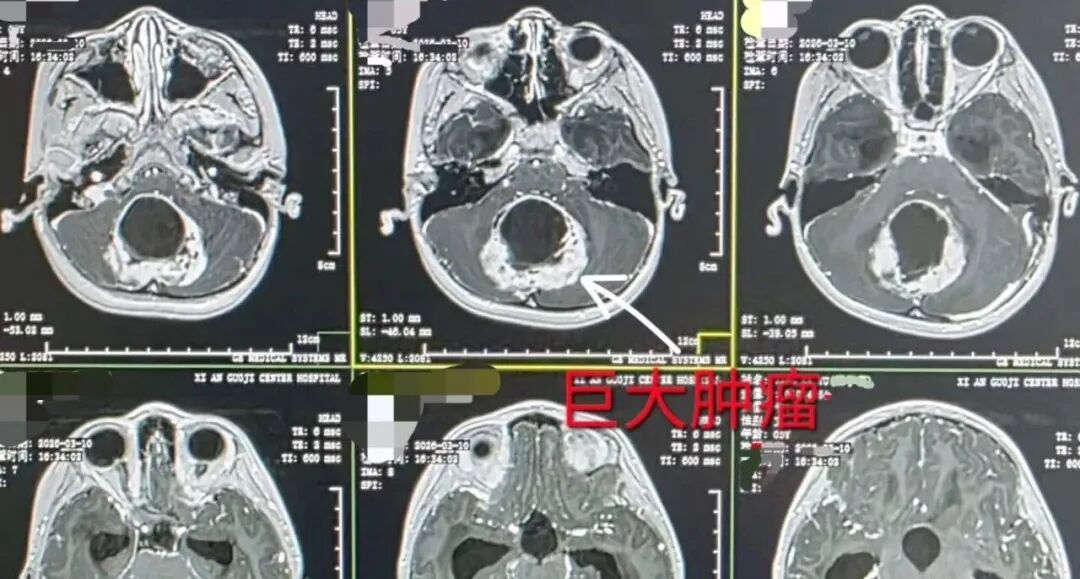

肿瘤加上它分泌液体形成的囊性包块,大小约 6.5×6×1.2 厘米,大小相当于一个苹果,几乎占据了颅内大部分空间,小脑被挤压得只剩下不到三分之一的空间。更棘手的是,这颗源于小脑蚓部的肿瘤已经向下延伸至椎管内颈 1 水平,不仅挤压着小脑和脑干,更严重压迫着延髓——那是控制心跳和呼吸的生命中枢。

(术前核磁)

「入院时孩子的颅压已经非常高,接近极限,而且延髓已经明显受压……」高亚飞医生神情凝重地向家属解释,「孩子有可能因为一个喷嚏、一次用力,就导致突发的呼吸、心跳骤停!」